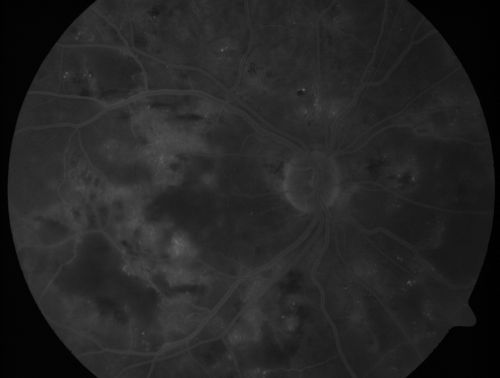

Diabetic Patient with Macular Edema and Blood Pressure 200/95

49-year-old decreasing vision over the last year. OD is 20/80, OS 20/80. blood pressure which was 200/95.

Hypertensive Retinopathy in a Diabetic

macular edema

cotton wool spots

diabetic

hypertensive